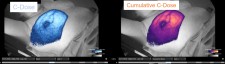

C-Dose captures the dim glow emitted from tissue during high energy radiation treatments to provide video rate images of the radiotherapy as it is delivered to the patient. Powerful software tools for image processing provides automated analysis of the treatment, with little to no impact to the current clinical workflow.